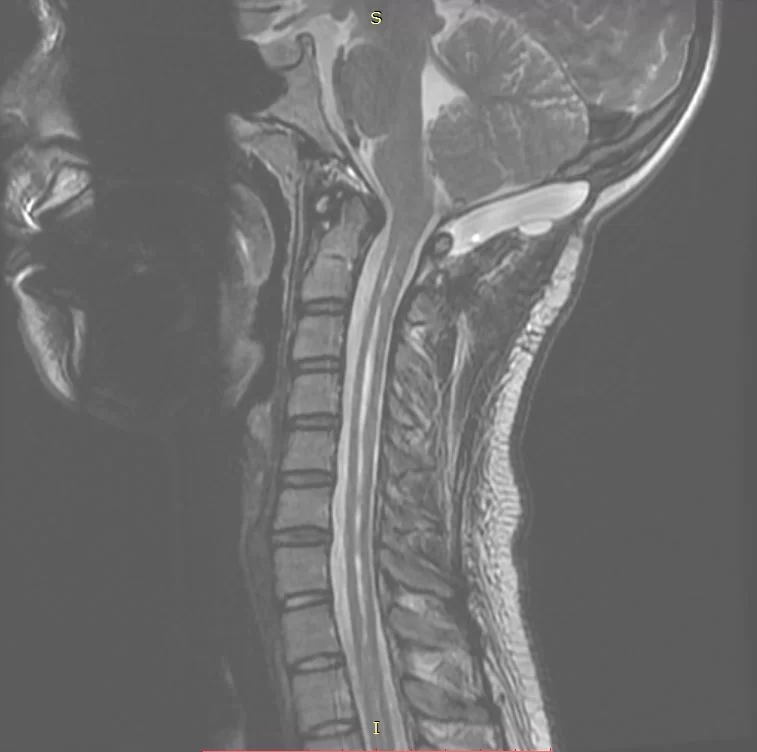

Νεαρή ασθενής 17 ετών με εκτεταμένη συριγγομυελία από την αυχενοπρομηκική συμβολή έως το τελικό τμήμα του νωτιαίου μυελού, λόγω συνδρόμου Chiari. Κλινικά αιμωδίες (μουδιάσματα) άνω άκρων, ζάλη.

Η μαγνητική τομογραφία περίπου 3 μήνες μετά το χειρουργείο δείχνει οτι οι αμυγδαλές της παρεγκεφαλίδας δεν καταδύονται πλέον πέραν του ινιακού τρήματος και -το κυριότερο- η συριγγομυελία έχει υποχωρήσει σημαντικά.

Το σύνδρομο Chiari είναι μια σχετικά σπάνια πάθηση στην οποία, στην πιο συχνή μορφή της, οι αμυγδαλές της παρεγκεφαλίδας, δηλαδή το τελικό τμήμα της παρεγκεφαλίδας κατεβαίνει πολύ χαμηλά στη βάση του κρανίου και περνά μέσα από το ινιακό τρήμα, δηλαδή την “τρύπα” μέσα από την οποία θα έπρεπε να περνά μόνο o νωτιαίος μυελός.

Αυτό έχει σαν αποτέλεσμα να διαταράσσεται η φυσιολογική κυκλοφορία του εγκεφαλονωτιαίου υγρού (ΕΝΥ), τόσο στον εγκέφαλο όσο και στο νωτιαίο μυελό, με συνέπεια τη συριγγομυελία (= ο κεντρικός σωλήνας του νωτιαιου μυελου διατείνεται και “γεμίζει” με νερό).